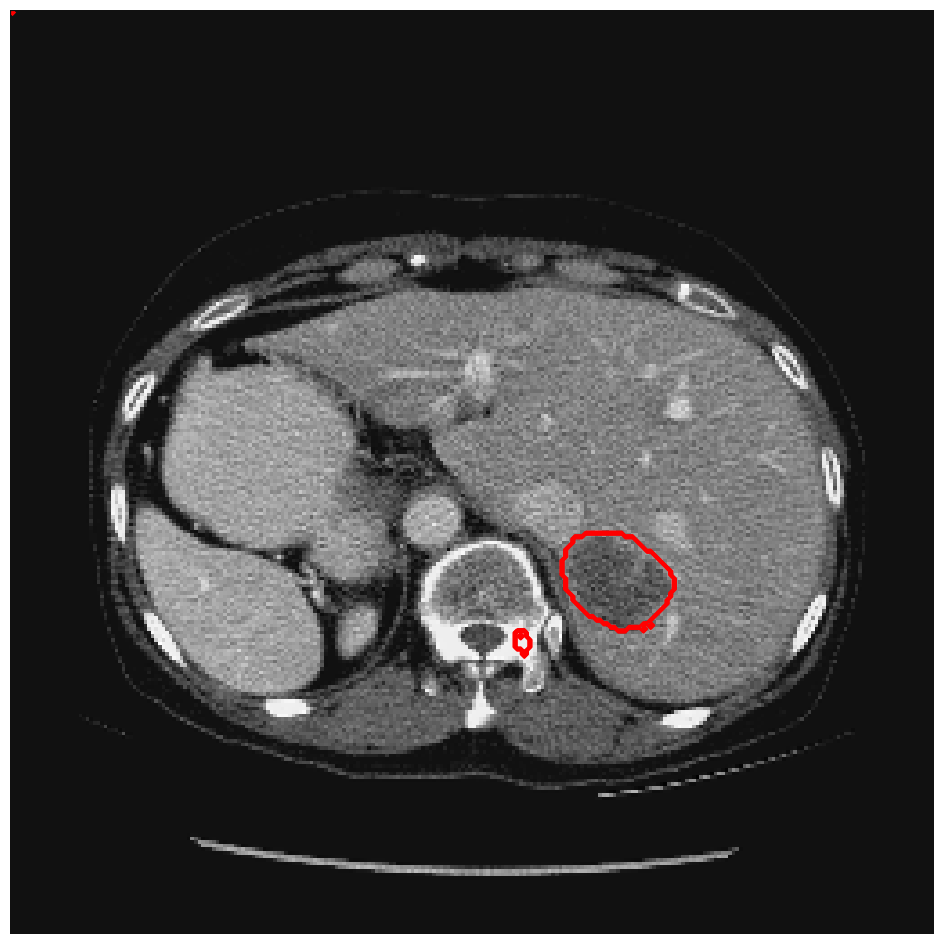

Figure 5: A sample result on the Liver data. We display the input image with the user input \mathcal{M}, the ground truth (GT) and results from the four methods. Moreover, we show comparisons with the model (4) solved in a variational framework with both Total Variation (TV) and Euler Elastica as explicit regularisation, as well as a comparison with the model solved in a Deep Image Prior framework.

Figure 6: A sample result on the Liver data. We display the input image with the user input \mathcal{M}, the ground truth (GT) and results from the four methods. Moreover, we show comparisons with the model (4) solved in a variational framework with both Total Variation (TV) and Euler Elastica as explicit regularisation, as well as a comparison with the model solved in a Deep Image Prior framework.